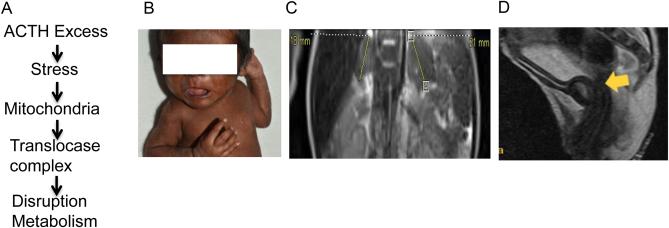

Steroid hormones are essential for the survival of all mammals. In adrenal glands and gonads, cytochrome P450 side chain cleavage enzyme (SCC or CYP11A1), catalyzes conversion of cholesterol to pregnenolone. We studied a patient with ambiguous genitalia by the absence of Müllerian ducts and the presence of an incompletely formed vagina, who had extremely high adrenocorticotropic hormone (ACTH) and reduced pregnenolone levels with enlarged adrenal glands. The testes revealed seminiferous tubules, stroma, rete testis with interstitial fibrosis and reduced number of germ cells. Electron microscopy showed that the patient's testicular mitochondrial size was small with little SCC expression within the mitochondria. The mitochondria were not close to the mitochondria-associated ER membrane (MAM), and cells were filled with the microfilaments. Our result revealed that absence of pregnenolone is associated with organelle stress, leading to altered protein organization that likely created steric hindrance in testicular cells. Learning points: Testes revealed seminiferous tubules, stroma, rete testis with interstitial fibrosis and reduced number of germ cells; Testicular mitochondrial size was small with little SCC expression within the mitochondria; Absence of pregnenolone is associated with organelle stress.

类固醇激素对所有哺乳动物的生存至关重要。在肾上腺和性腺中,细胞色素P450侧链裂解酶(SCC或CYP11A1)催化胆固醇转化为孕烯醇酮。我们研究了一名生殖器模糊的患者,其苗勒管缺如且阴道发育不完全,促肾上腺皮质激素(ACTH)水平极高,孕烯醇酮水平降低,肾上腺增大。睾丸可见生精小管、间质、睾丸网伴间质纤维化,生殖细胞数量减少。电子显微镜显示,患者睾丸线粒体体积小,线粒体内SCC表达极少。线粒体未靠近线粒体相关内质网膜(MAM),细胞内充满微丝。我们的结果表明,孕烯醇酮缺乏与细胞器应激有关,导致蛋白质组织改变,可能在睾丸细胞中造成空间位阻。学习要点:睾丸可见生精小管、间质、睾丸网伴间质纤维化,生殖细胞数量减少;睾丸线粒体体积小,线粒体内SCC表达极少;孕烯醇酮缺乏与细胞器应激有关。